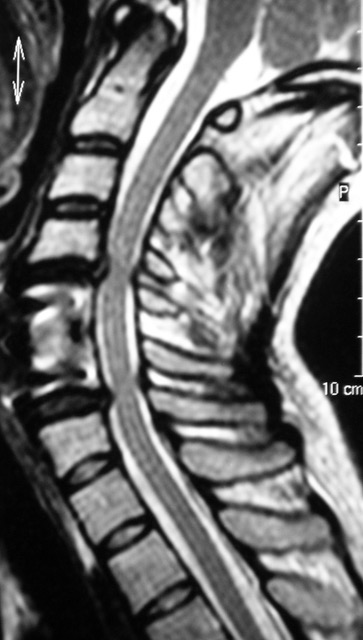

- Resonancia Magnética (RM): Es el estudio de elección, ya que permite visualizar directamente la médula espinal y las estructuras circundantes. Muestra el grado y la ubicación de la compresión (discos herniados, osteofitos, engrosamiento ligamentoso), así como cambios en la señal intramedular (mielomalacia o edema), que se correlacionan con peores resultados quirúrgicos.